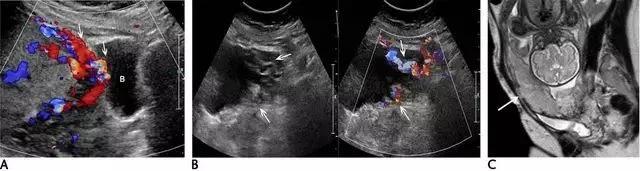

胎盘附着异常:包括胎盘粘连、胎盘植入及胎盘穿透(图 11)。胎盘粘连指胎盘组织向子宫肌壁延伸,但并未对其构成实质性的侵袭,占所有胎盘附着异常的75%。

胎盘植入指胎盘组织已侵入子宫肌壁,但并未突破浆膜层。穿透指不仅侵入肌壁,且已突破至浆膜层之外,可导致子宫的毗邻器官如膀胱、肠管及腹壁受累。超声是本病的主要显像方法,在临床高度怀疑本病或超声检查为阴性或不确定时,可使用 MRI(图 12 和图 13)。

图 12 示胎盘粘连:A 为孕 32 周患完全性前置胎盘(此图未显示)孕妇的子宫前壁横切面(线阵探头所得),可见肌壁由上至下、向膀胱子宫陷凹方向逐渐缺乏、变薄(短箭头所示)。B 为另一孕妇的冠状位 MRI,孕期经常性左腹痛,超声考虑胎盘粘连,长箭头示胎盘下方的低信号肌壁由左向右逐渐变薄。此 2 例均在剖腹产时被证实为胎盘粘连

图 13 示合并有完全性前置胎盘的胎盘穿透,患者有 2 次剖宫产病史:A 为子宫纵切面,箭头示肌壁逐渐变薄、子宫与膀胱之间的界限模糊,胎盘下的闲置空间消失(B :膀胱)。B 为同一患者的子宫矢状面,箭头示大量不规则紊乱血流向肌壁延伸。图 C 为另一孕妇 28 周时的矢状位 MRI,可见前次剖腹产瘢痕上缘存在胎盘对子宫前壁的侵犯、肌壁连续性局部中断(箭头)